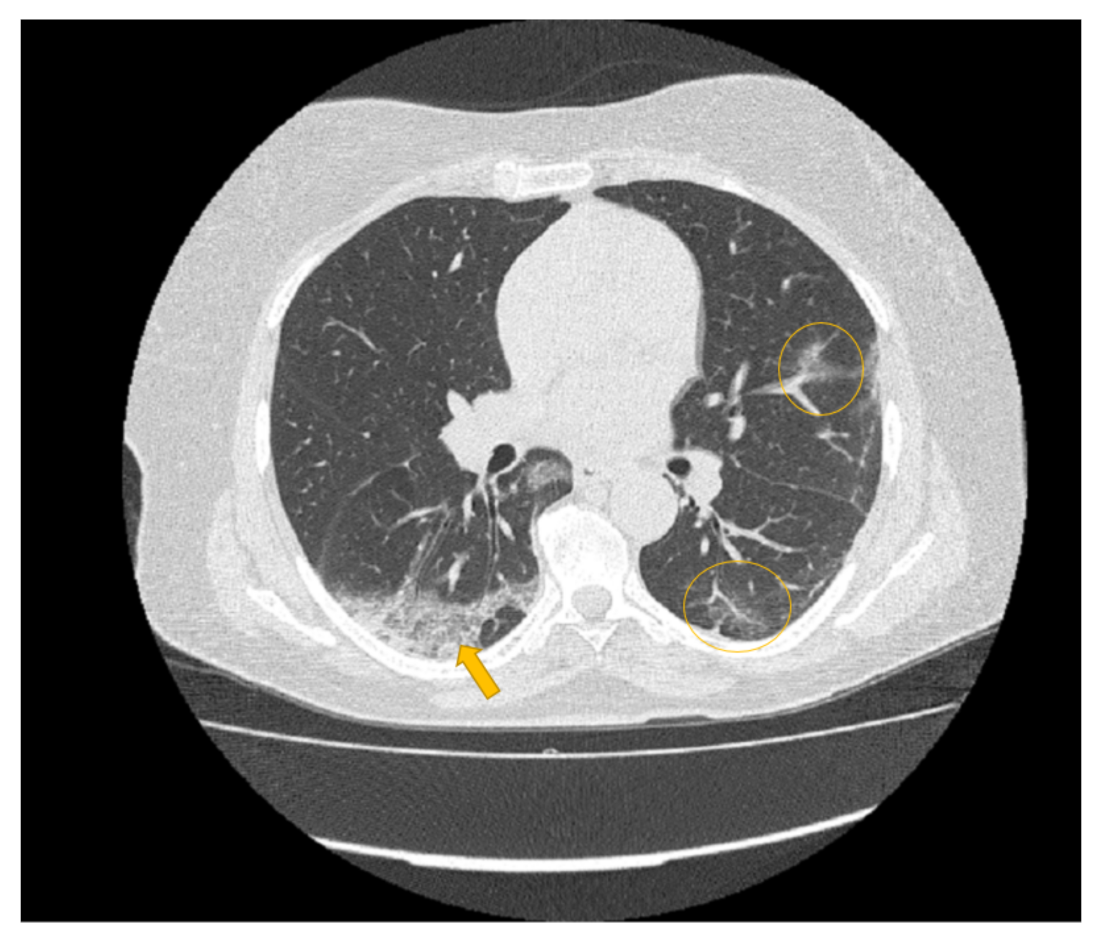

Every medical image is a combination of grey-levels that produce the morphology of the image. In this specific case, the attention is focused on HRCT images of the lung. In particular, the external part of a healthy lung would be white, while the inner part of the lung would be black. In this black part there could be different movements that display normal respiration and the performance of vital functions. Through these images, in the black section of the lung, radiologists can note some white spots that can be marked as disease symptoms, but they would not know to which disease the marks refer. For example, in Figure 5, Figure 6 and Figure 7 there are three different HRCT belonging to three different patients: one image has ”very black” lungs, while the others have some white spots. As a matter of fact, the Figure 5 is an HRCT of a healthy patient and it does not show white spots or pneumonia signs. The Figure 6 and Figure 7 are similar, because they both show some disease marks: the first is from a COVID-19 patient, while the second is from a lung disease patient. Thanks to this, it is clear just how difficult it is to see the differences between a general pneumonia and Coronavirus disease with the naked eye.

Figure 6. HRCT scan of a COVID-19 patient. The image revealed a lesion in the form of “crazy paving” seen in the right lung lower lobe with peripheral distribution (yellow arrow) and ground glass opacity seen in the left lower lobe (yellow circles) peripheral and central distribution.